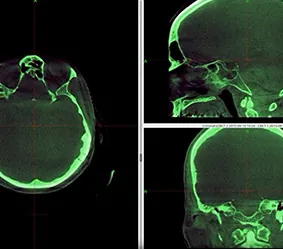

STEREOTACTIC SURGERY – TREATMENT PLANNING

Leksell GammaPlan